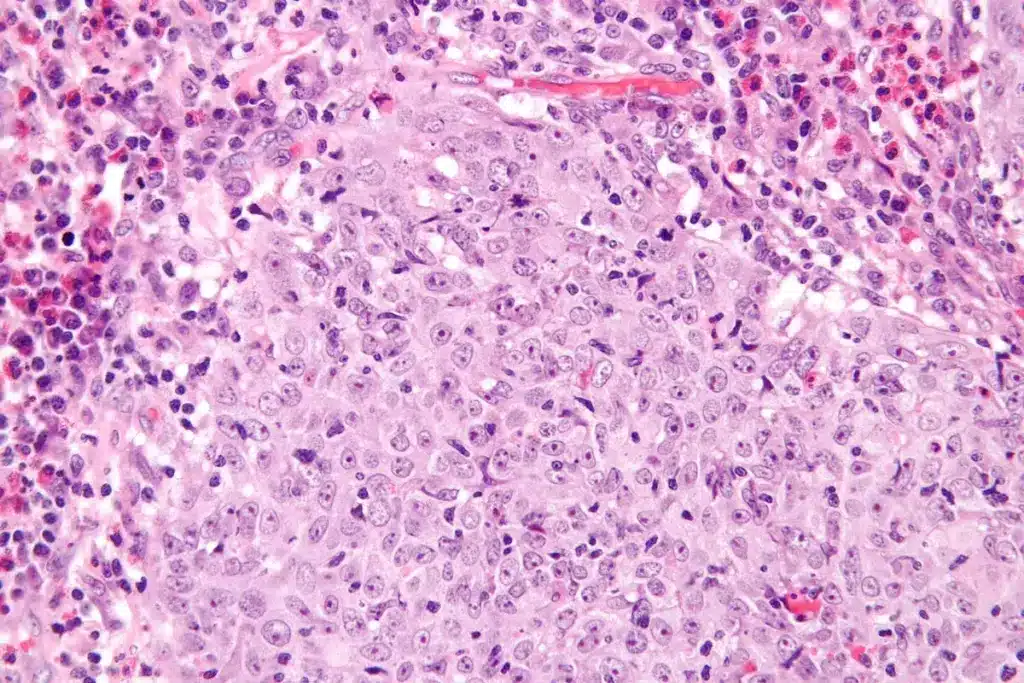

Biopsy Techniques and Pathological Examination

Biopsy is the top method for diagnosing squamous cell carcinoma. We use several biopsy techniques, such as:

- Fine-needle aspiration biopsy: Good for checking suspicious lymph nodes or lesions.

- Core needle biopsy: Gives a bigger tissue sample for detailed histological study.

- Surgical biopsy: Removes a larger tissue sample or the whole tumor for thorough analysis.

Examining biopsy samples is vital for confirming the diagnosis. It helps identify tumor characteristics and guides treatment choices.